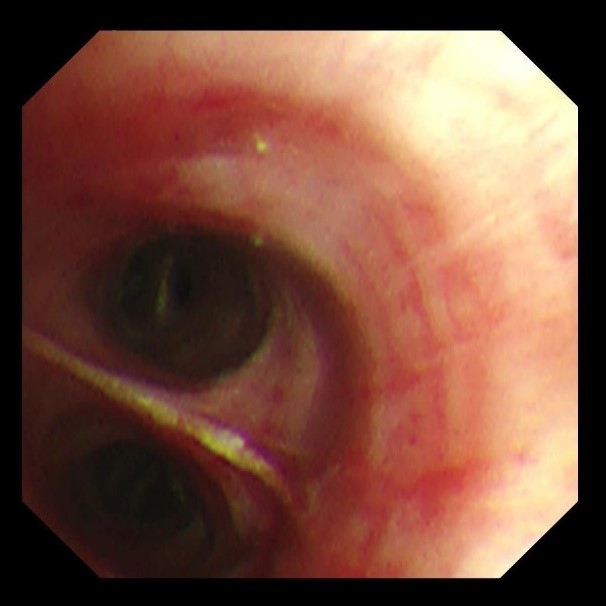

两天后复查支气管镜,发现患者左下叶背段远端细支气管仍有残留泥沙样异物。团队采用超细支气管镜联合冷冻技术,通过冷冻探头将异物凝固,再用超细活检钳逐支清理,实现对远端气道的彻底清理,实现气道“零死角”。

(远端支气管治疗后)